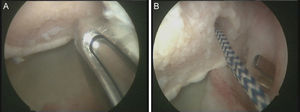

No es estrictamente necesario que reproduzcamos un enganche de la lesión de Hill-Sachs inversa para decidir realizar el remplissage inverso. Con la óptica en el portal anterosuperolateral liberamos el tendón del subescapular, su cara anterior y posterior. Preparamos el lecho óseo de la cabeza humeral, extirpando todo el tejido fibroso de la lesión de Hill-Sachs inversa, con el sinoviotomo, la fresa de hueso o periostotomos, hasta obtener hueso sangrante. Entonces desde el portal anterior, insertamos los implante en el defecto óseo (en el caso 1 un 5,5 Healix BR [DePuy Mitek, Raynham, MA] con 2 suturas UHMWPE [Orthocord; DePuy Mitek]) en el tercio superior y en la zona más medial del defecto (fig. 5), y en el caso 2 insertamos 2 Gryphon BR Healix BR (DePuy Mitek, Raynham, MA) con 2 suturas UHMWPE (Orthocord; DePuy Mitek), uno inferior y otro superior en la zona más medial del defecto óseo. Recuperaremos las suturas desde un portal anterosuperior accesorio y con una pinza para atravesar el tendón (Penetratror DePuy Mitek, Raynham, MA) a través del portal anterior, atravesamos el tendón del subescapular y recuperamos las suturas. Daremos puntos colchoneros, uno inferior y otro superior, para conseguir un buen contacto del tendón con el hueso, separando los puntos entre 1 y 2cm (fig. 6). Podemos ayudarnos con un empujanudos a través del portal anterosuperior accesorio para el manejo y recuperación de las suturas, acercándolas a la boca de la pinza penetrator, tratando de no mover en exceso la pinza una vez atravesado el tendón, para evitar lesionar el tendón y el cartílago. Manteniendo el brazo en 35-40° de rotación interna anudamos primero el punto inferior y luego el superior (figs. 7 y 8).

Caso 1, hombro derecho. A. Vista desde el portal ASL de la lesión de Hill-Sachs inversa con el implante en el tercio medial del defecto óseo. B. Imagen después de hacer los nudos; podemos ver el tendón del subescapular rellenando parcialmente el defecto óseo de la cabeza humeral, con la cabeza centrada en la cavidad.